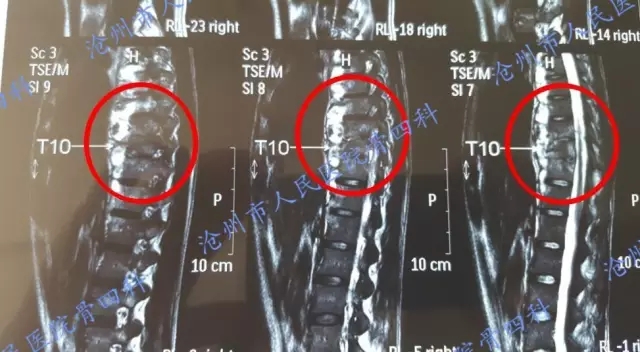

手术前影像学检查:

3、 门诊检查:胸椎CT显示:多节胸椎骨质破坏;软组织周围脓肿形成。 T36.7℃ P90次/分 R20次/分 Bp 120/80mmHg。专科检查:患者平卧位,脊柱无明显畸形,胸椎约T9~T11水平压痛叩击痛,无放射痛,局部皮肤未见红肿及包块,四肢各关节活动正常,肌力、肌张力正常,双下肢皮肤感觉正常,末梢血运可。